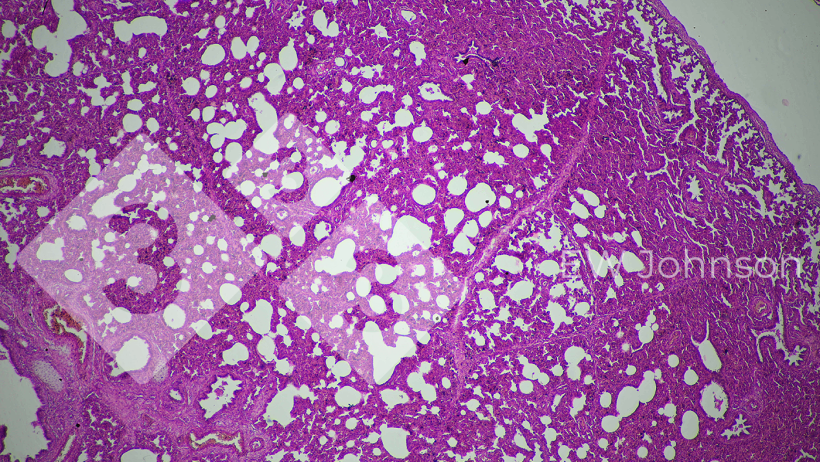

A PCR foi negativa para PRRS, PRV, doença de Aujeszky, circovírus suínos PCV2 e PCV3, Peste Suína Clássica (PSC) e Peste Suína Africana (PSA). A exploração era conhecida por estar livre de PRRS, PRV, PSC e PSA antes deste evento. A PCR para Getahvirus em pulmão de leitão foi altamente positiva. A histopatologia revelou pneumonia intersticial grave (Figura 3) e meningoencefalite fibrinohaemorrágica (Figura 4). A doença perinatal por Getahvirus foi diagnosticada. A exploração foi informada de que esta doença é principalmente transmitida por mosquitos e foram implementadas medidas de controlo. Não houve mais casos ou sinais clínicos na exploração pecuária e a produção voltou ao normal.

Figura 3. A pneumonia intersticial sugere uma possível origem viral.